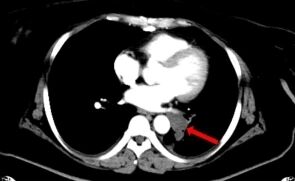

左肺下叶肿瘤 右肺下叶结节

患者许某,女性,41岁,因“骨盆软骨肉瘤术后2年,发现双肺多发结节”就诊。影像学检查提示,其双肺及胸膜下存在多发结节及肿块,尤其是左肺下叶一处病灶,位置特殊,紧邻上腔静脉及左心室等重要大血管结构。明确这些病灶的性质是决定后续治疗方案(包括是否适合重离子放疗等先进治疗)的关键,但常规穿刺路径风险极高,稍有不慎即可能引发出血等严重并发症。

2026年1月24日,在充分的术前准备和讨论后,手术正式开始。患者取俯卧位,采用负压垫进行体位固定,确保术中体位稳定。首先行增强CT扫描,精确勾画出靶病灶与周围血管的立体关系,规划出最优穿刺路径,避开重要结构,并在体表做好精准标识。在局部麻醉下,郭福新教授凭借娴熟的手法,在CT实时引导下,将活检针精准、平稳地经皮穿刺至预定靶点。术中多次扫描确认针尖位置无误,成功获取了高质量的组织标本。整个操作过程流畅,术中及术后即刻复查未见气胸、出血等并发症,实现了对高风险病灶的“毫米级”精准狙击。